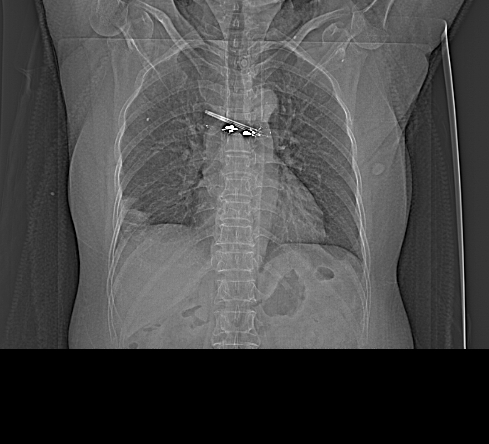

以下是引用余辉在2009-2-19 20:10:00的发言:[br]多考虑急性感染性病变,右中叶尚可见多枚小斑片状影,多为化脓性肺炎,双侧胸腔积液

以下是引用随光逐影在2009-2-19 20:33:00的发言:[br]1)考虑右肺炎症;建议抗炎治疗后复查。2)双侧胸腔积液(以右侧为甚)。

以下是引用花凤凰在2009-2-19 20:46:00的发言:[br]病人有发热,胸痛急性起病,主要病变位于右肺中叶外侧段,呈楔行改变,位于外带胸膜下,考虑为肺梗塞可能!!!!!!!!!!!!!!!!!!!!!!!!!!!!!!!!!!!